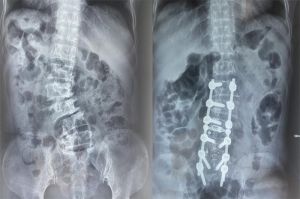

Phẫu thuật chỉnh nắn cột sống cho bệnh nhân vẹo cột sống suốt 12 năm